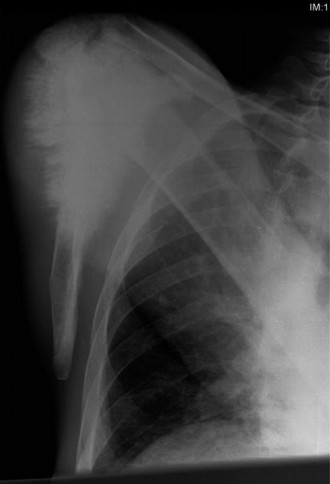

A 44-year-old, right-hand-dominant male with well-controlled diabetes and hypertension presents to clinic wit…